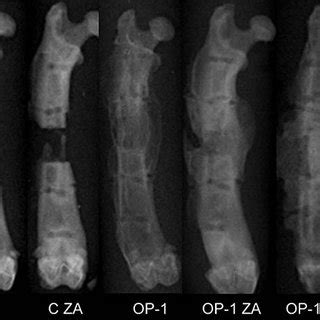

Generation of cartilaginous and periosteal bony callus. Callus varies significantly in form and texture, ranging from hard nodular cell masses to friable soft ones. E) dead portions of bone fragments are resorbed by osteoblasts.answer: Page 188, exercise and bone tissuelevel of difficulty: Which of the following is the largest and most complex level of organization in the body? The shape of the individual cells within the. Thus, it does not usually occur naturally, but rather following. They are made in the bone marrow from. It may be white or creamish, green either in whole or in part of the chloroplast development, or purple due to anthocyanin accumulation in the vacuoles. Bone cells with no nutrition will die and area will become irritated. A cartilage callus forms that holds together the two broken ends of the bone. There are numerous each with their own function. Fibroblasts give rise to chondrocytes that differentiate and form cartilage. After birth or shortly after, most hyaline cartilage models have been a hematoma is formed, the break is splinted by a fibrocatilage callus,the bony callus is formed, bone remodeling occurs. Hematoma formation, fibrocartilaginous callus formation, bony callus formation, and remodeling. Bone forming cells called osteoblasts. Cells come from preexisting cells.